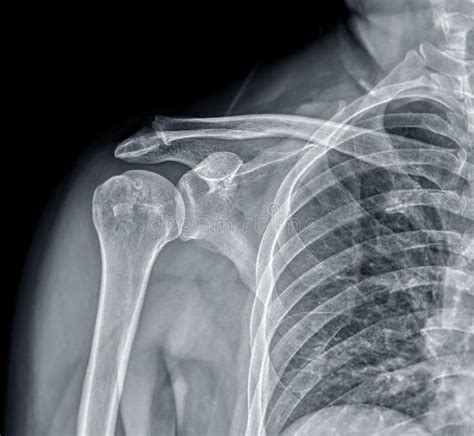

Understand how to identify a healthy joint with our guide on an X-ray shoulder normal. Learn to recognize standard anatomical landmarks, including the glenohumeral joint, acromioclavicular alignment, and bone density. This clinical overview helps patients and students interpret diagnostic imaging, identify common skeletal structures, and distinguish normal radiographic findings from potential shoulder injuries or pathology.